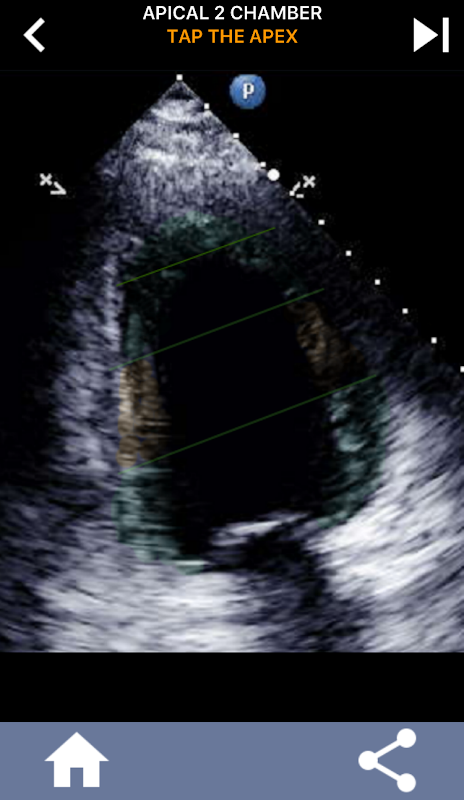

تعلم بسرعة AHA 17 قطعة نموذج القلب، من الضروري لجميع صدى الطلاب!

من الضروري أن يتعلم مخطّط ضربات القلب بالموجات فوق الصوتية تجزئة القلب من جمعية القلب الأمريكية من البطين الأيسر إلى 17 قطعة وهو المعيار المستخدم على نطاق واسع من قبل العديد من طرائق التصوير الأخرى مثل التصوير بالرنين المغناطيسي والاختبارات النووية للقلب وما إلى ذلك. من الشرائح المتضررة وظيفة. في كثير من الأحيان يسأل الشخص الذي يقرأ صدى "ماذا رأيت؟" والرد مع الموقع الدقيق للمنطقة المتأثرة هو ما هو متوقع.

يحتوي هذا التطبيق على جميع طرق عرض الصدى التي تُظهر عضلة القلب المفصَّلة AHA وسيختبرك للاستفادة من الجزء الصحيح. أنا شخصيا أجد أن الاختبارات المتكررة تعمل بشكل أفضل بالنسبة لي عندما أحتاج إلى تعلم / حفظ الموضوع بسرعة. إذا كنت طالبًا بالموجات فوق الصوتية يدرس الارتداد / أعتقد أن هذا سيكون مكملاً ممتازًا لدراستك.